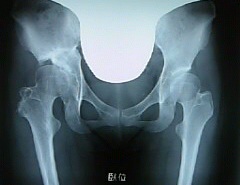

そして画像が今日のレントゲンでーす。

前回とそんなに変わってないような。

主治医からも特に問題はなしですね、と言われ今日の診察は終わりました。